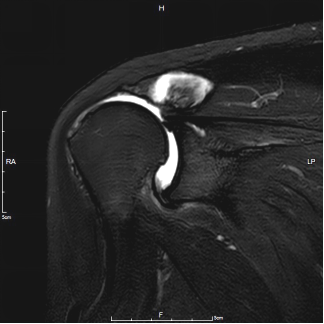

通过详细而周密的查体动作,王少杰教授判断该患者应该属于肩袖撕裂,而非肩周炎,并通过核磁共振检查明确了肩袖断裂的诊断和肩袖断裂的范围。但是,王大爷的情况已相当严重,王少杰教授介绍说:“患者肩袖肌腱断裂三根,且损伤时间较久,以致于构成肩袖结构的冈上肌腱及冈下肌腱已经基本消失了,肌肉组织被大量脂肪所浸润,属于不可修复肩袖撕裂,已无可能采用传统的关节镜下手术修补。”

(患者术前核磁共振检查提示巨大肩袖破裂)